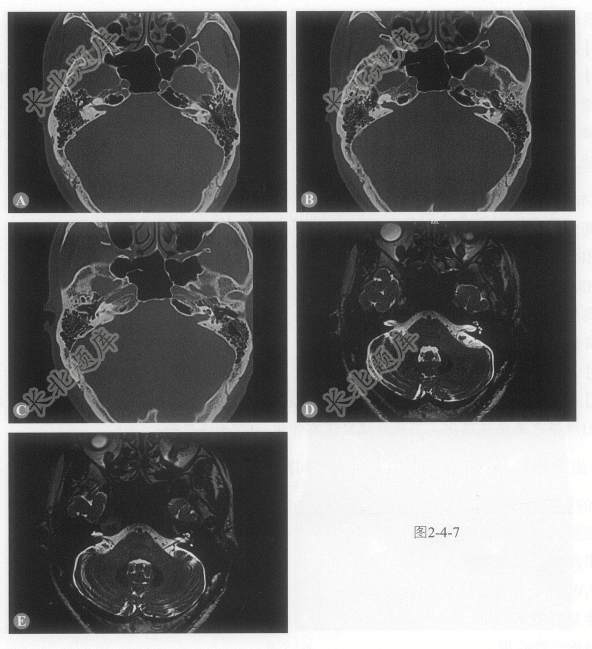

患者男性,39岁,右耳听力下降8年,CT和MRI表现如图2-4-7。

- 多项选择题1.该病发生的部位为:

- 多项选择题2.该病的诊断为:

- 多项选择题3.下面有关本病说法正确的是:

- 多项选择题4.关于本病影像方法选择正确的是:

A、高分辨MRI T2WI是最好的检查方法

B、HRCT可以显示早期病变

C、HRCT仅可显示晚期病变

D、高分辨MRI不能显示早期病变

E、高分辨增强MRI T

WI可显示早期病变